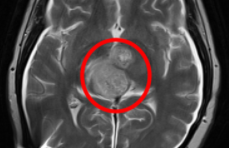

南開大學化學學院陳悅教授課題組原創(chuàng)新藥ACT001臨床試驗結(jié)果公布

ACT001針對惡性膠質(zhì)瘤這個世界醫(yī)學難題,其臨床試驗結(jié)果由中外醫(yī)生先后公布于美國臨床腫瘤學會ASCO與神經(jīng)腫瘤學會SNO...